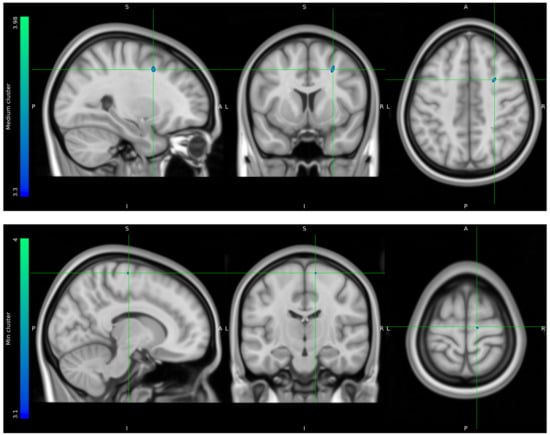

Due to data loss on the scanner, only 8 HCs and 10 stress patients were included in the brain imaging analysis. The one-tailed t-tests performed to evaluate voxels for which there was a directional-specific group difference (i.e., HC > stress or HC < stress) only showed effects in the HC > stress group. The one-tailed t-tests evaluating voxels for which there was a directional-specific group difference driven by a hypometabolic effect in stress patients compared to HCs identified three clusters with MNI coordinates [−30 24 24], left frontal lobe sub-gyral adjacent to middle frontal gyrus, [28 8 44] right frontal lobe middle frontal gyrus, and [12 −16 68] right frontal lobe precentral gyrus. Noticeably, the identified cluster appeared primarily to be located in the WM regions (Figure 5).

Figure 5.

FDG uptake illustrating a difference in glucose consumption between stress patients and healthy controls. Here, projected on MNI standard space template MNI152 0.5 with intensity threshold defined in color bar on the left. A: anterior, P: posterior, S: superior, I: inferior, L: left, R: right.

Mean FDG uptake values were extracted from suprathreshold clusters for visualization from each participant (Supplementary Materials S4). Value distributions are illustrated in the box plots (Figure 6).

Mean cluster estimates subtracted from single-subject glucose consumption in the maximum cluster of the hypometabolic effect t-test.

The results of the adapted version of the SCAN interview showed a clinical direction of stress patients experiencing physiological dysfunction as well as mental challenges in higher brain functions related to executive functions and emotion and mood regulation. Our FDG-PET imaging group analysis identified three clusters of voxel-wise differences in cerebral glucose metabolism between stress patients and HCs, where the stress patients had hypometabolic effects in areas primarily located in the white matter of the prefrontal cortex. The extracted suprathreshold cluster mean FDG uptake values for each participant expresses a consistent difference in the distribution between stress patients and HCs.